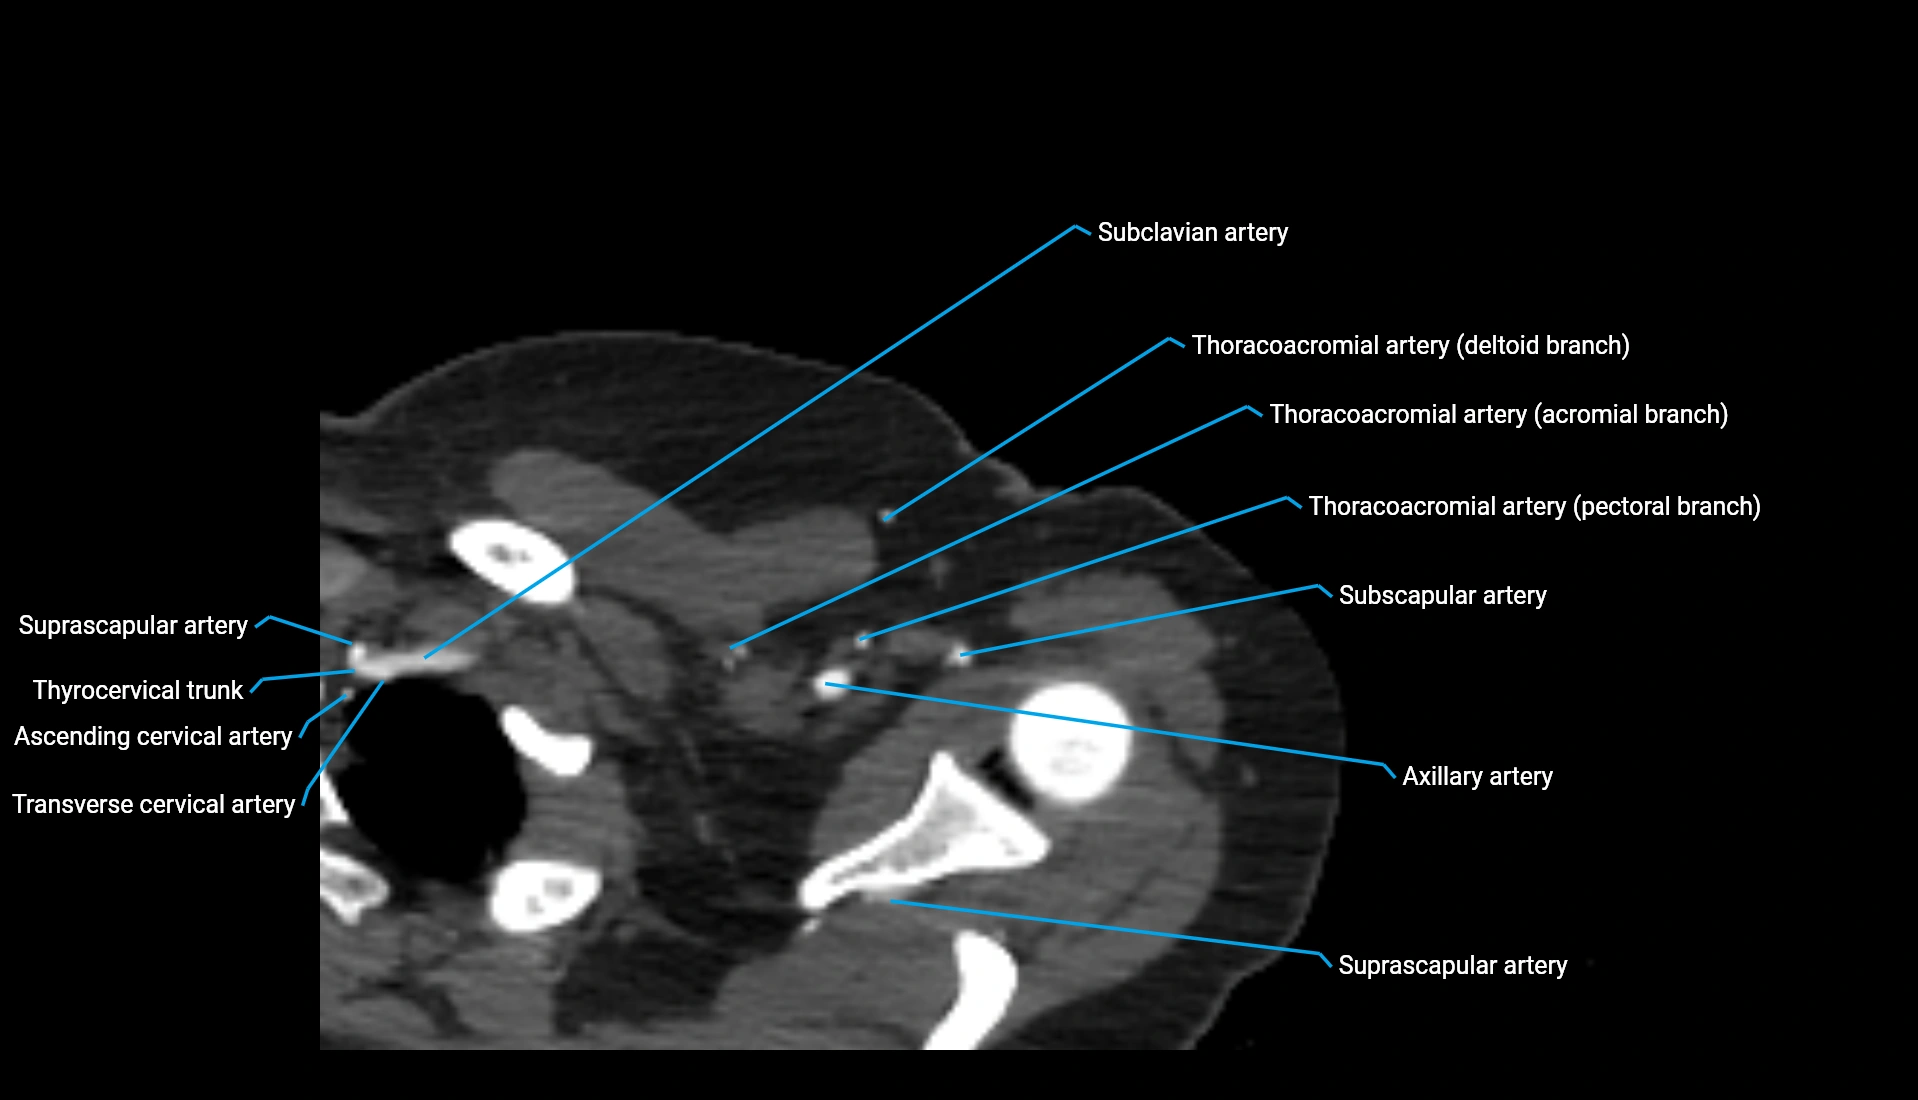

CT Appearance

Non-Contrast CT:

• Cortex: High-density, sharply defined

• Subchondral bone: Dense cancellous matrix

• Articular surface: Smooth concave contour articulating with the capitellum

• Excellent for evaluating bone integrity, alignment, and subtle fractures

Post-Contrast CT:

• Bone: No enhancement

• Joint capsule and synovium: Mild enhancement outlining the joint

• Improves contrast between soft tissues and bony margins

• Useful in detecting subtle joint abnormalities or postoperative changes